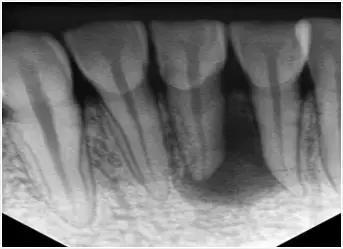

在根管治疗术前对牙齿拍X光片,以帮助诊断牙齿髓室的位置、根管数目及形态、测量根管工作长度以及为评价治疗效果提供对比的依据。

应用平行投照X光方法、根管长度测量仪确定根管长度,较 好插针拍X片。

封闭整个根管系统、堵塞主根管和侧副根管出口、防止微生物和液体的渗漏。无论是侧方加压法还是垂直加压法,应做到根管充填致密,根管充填后X光片上无根管腔隙,也不能超出根尖孔。

X光片显示根管充填完好,可进行暂时或永久牙体修复,带上牙冠,保护患牙。至此根管治疗才可算完成,同时根管治疗后还需复诊,一般周期可为3个月、半年、1年、2年或更长。